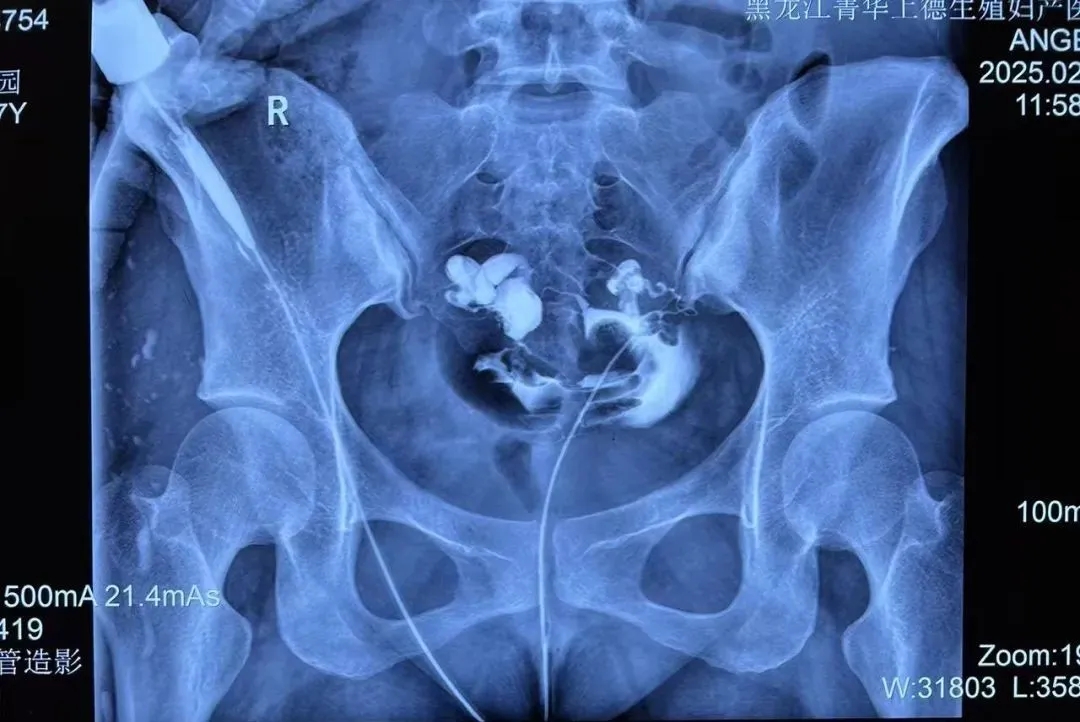

2月16日上午,手术正式开始。术中马院长耐心、细致进行手术操作,最大程度减少对子宫及输卵管的损伤,手术顺利完成。患者术后当日便下床活动,恢复状况良好。

宫腔镜下输卵管栓塞术是一种新兴的微创技术。通过经阴道内镜的方式,医生可以清晰观察到宫腔内环境,同时定位到输卵管的开口,手术中通过专门的设备将细小的微弹簧圈送入输卵管,达到栓塞的效果。具有显著优势:

✅ 精准阻断:栓塞材料永久性封堵输卵管,彻底避免积液反流干扰胚胎。